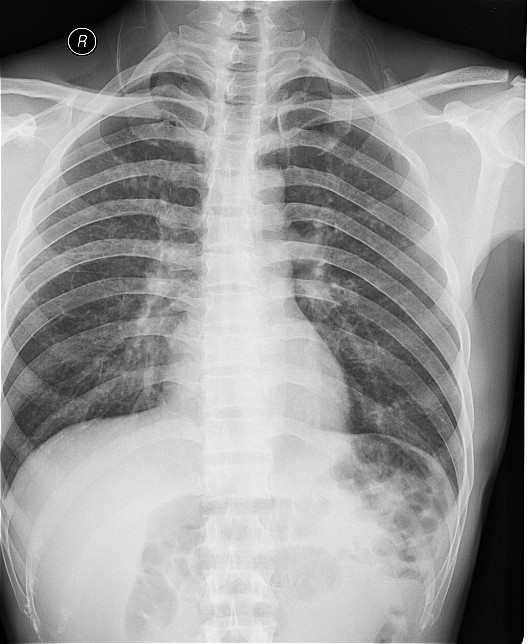

一钨矿工厂因有毒气体泄漏(据说是硝酸)造成十多名工人中毒,均出现不同程度的咳嗽,气逼,心跳加快等中毒症状.其中有几例患者胸片出现小点片状,结节状阴影.是此次中毒引起的肺部改变还是原来就患有矽肺病或其它病变.

肺水肿,及原来就患有矽肺病

原就有的矽肺,未见中毒性肺水肿

支持矽肺,未见肺水肿.建议治疗后复查

矽肺,部分胸片可见肺水肿。治疗复查